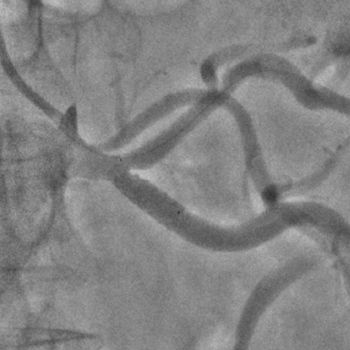

Бифуркационное стентирование почечной артерии

Ангиографическое исследование аорты и селективная ангиография сосудов почек выявило критический стеноз a. segmenti inferioris и короткую a. renalis sinistra

Операторы: Андрей Мальцев, Дмитрий Лебедев